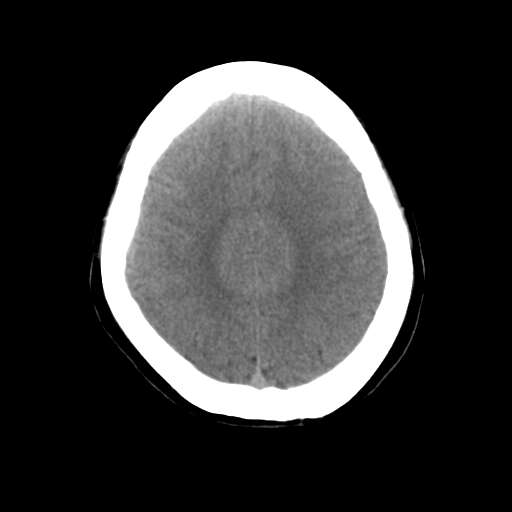

一台GE CT机突然出现下图伪影,请问是何原因?

并不是一直都有此伪影

这是设备原因造成的伪影一种伪影,

需要重新校准,

若不能矫正的话,那就没什么好办法了,

除非换配件

是不是原配球管啊,我院有台机器外圈有伪影是球管原因.

这种伪影一般还有个特点

在做薄层扫面时容易出现,一般是小于5mm,

但是在做常规10mm扫面时不会出现

这种现象并非一直出现,不分时间段,球管是租赁的,可能与电源有关

你有做一套的模和空气校正吗?没做好也会出这种情况的,一样是会有时好时坏的故障出的。